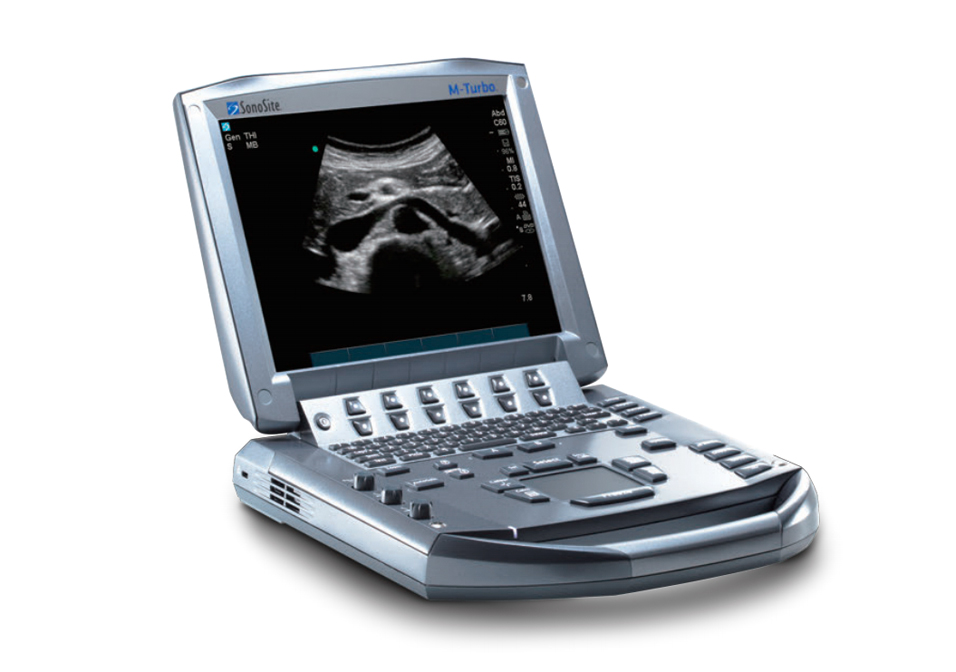

索諾聲M-TURBO

- 品牌索諾聲M-TURBO

M-Turbo 便攜式彩色超聲診斷系統(tǒng),源自嚴苛的設計標 準,以優(yōu)異的圖像質量和產(chǎn)品性能,引領POC可視化超 聲應用領域發(fā)展,讓醫(yī)生更從容地將更細致入微的醫(yī)療關護帶給患者。

10.4"屏幕尺寸,SonoADAPTTM 技 術 AutoGainM 技術 調節(jié)更為簡便 |